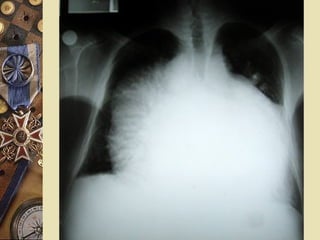

ELECTROCARDIOGRAMAELECTROCARDIOGRAMA

Alternancia eléctrica

 Signo de la

cantimplora